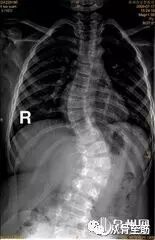

X光片虽不能作为确诊腰椎间盘突出症的依据,但可以排除某些疾患,如腰椎结核、腰椎肿瘤、脊柱滑脱、峡部裂、骶椎隐裂、腰椎骶化、骶椎腰化等。可以观察腰椎有无侧弯,腰前凸有无消失、椎体有无骨桥形成等。因为引起腰腿痛的原因有很多,所以需要通过X光片以初步排除这些情况。